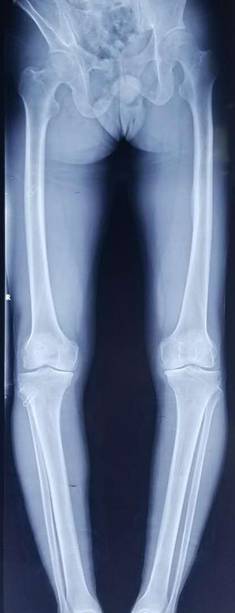

术前术后对比

全膝关节翻修术

全髋关节翻修术